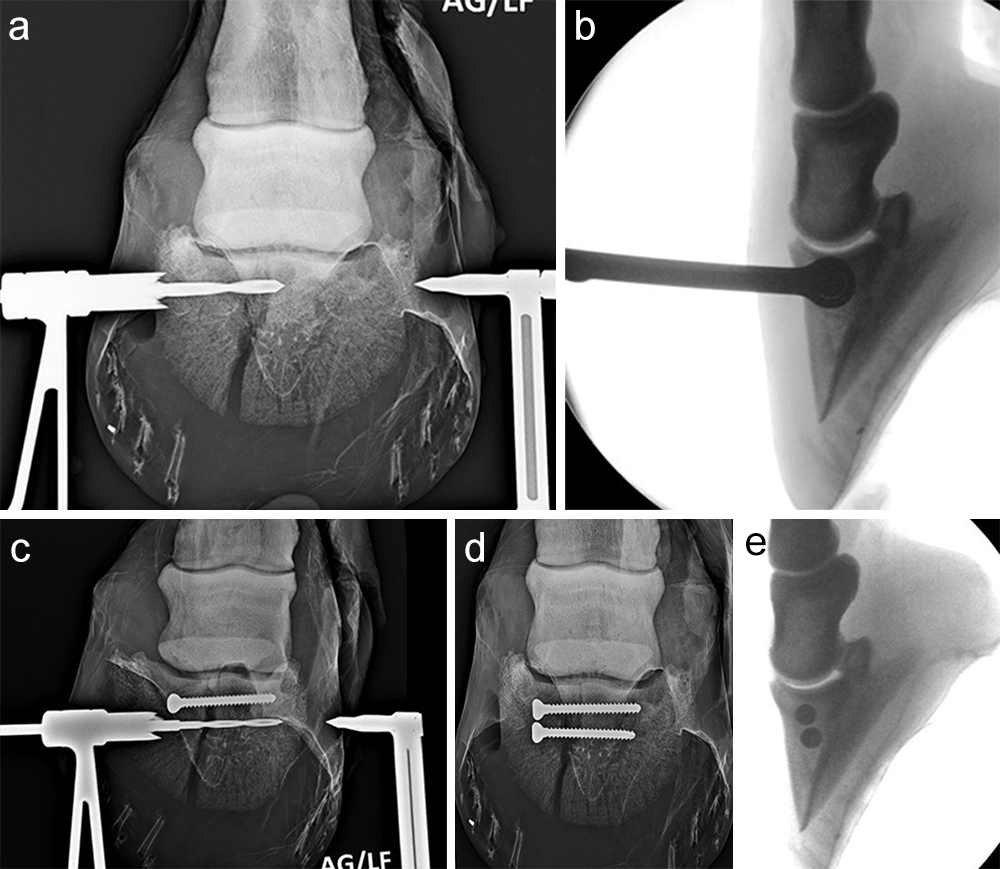

The horse was routinely anesthetized and positioned in left lateral recumbency to be able to access the medial aspect of the left forelimb. The lower limb was aseptically prepared and draped appropriately to isolate the solar region of the hoof from the surgical area, and to allow visualization of the coronary band. The targeting clamp was assembled with the straight outer sleeve and the 4.5 mm drill sleeve. It was positioned under radiographic and image intensifier guidance in an oblique direction to avoid drilling through the proximal hoof wall. Once the surgeons were satisfied with the position of the targeting clamp, the location of the trocar was marked on the draping and a stab incision was made at the level of the outer sleeve. The outer sleeve was inserted in the skin incision and the adjustable rail of the targeting clamp was tightened. The 4.5/3.2 mm insert sleeve followed by the 3.2/1.6 mm insert sleeve (provided in the 4.5 mm headless compression screw kit) were placed in the 4.5 mm drill sleeve (Fig 7).

A 1.6 mm guide wire was advanced through the bone to assess the correct positioning of the targeting clamp. The guide wire is centered within the cyst. At this stage, the ideal screw length was measured on the perioperative radiographs. When using these headless cannulated compression screws, remember that the shaft thread length is approximately 40% of the screw length. Ideally, the threaded shaft of the screw is positioned on the trans-side of the cyst. The 3.2/1.6 mm insert sleeve was then removed and the bone was drilled with a cannulated 3.2 mm drill bit to the required length (Fig 8a). Considering the high-bone density at this location, the entire length of the drill hole was tapped by hand with a cannulated 4.5 mm tap through the 4.5 mm drill sleeve. Next, a 4.5 mm headless compression screw was inserted through the 4.5 mm drill sleeve and tightened by hand (Fig 8b). The stab incision was closed routinely. The horse was covered with a two-layer bandage. The total surgery time was 30 minutes.